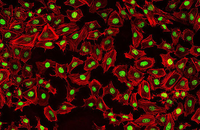

- Differentiation of cultured cells into different cell lines

- Confirmation of the nature of differentiated cells by ICC method